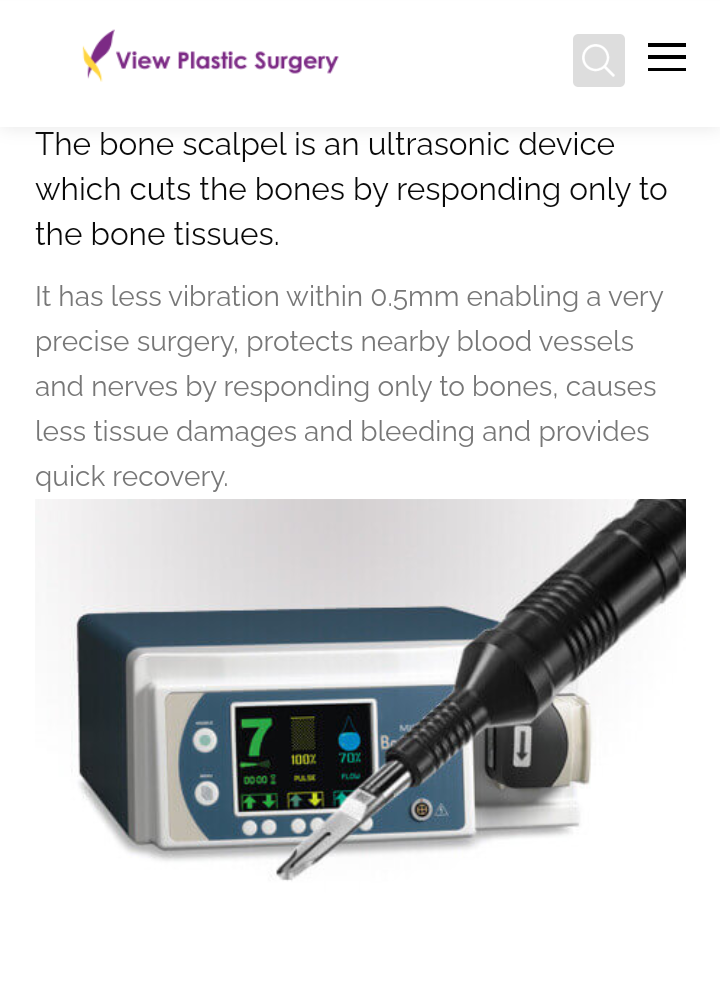

Its because of stuff they use to perform surgery

Ultrasonic bone scalpel is great because only affect bone tissues. Make it safer.

And that all possible due to unique scalpel and technique.

But how its possible to cut centre of maxilla?

Its because of stuff they use to perform surgery

Ultrasonic bone scalpel is great because only affect bone tissues. Make it safer.

And that all possible due to unique scalpel and technique.